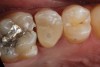

(4.) Preparation of tooth No. 19 with 4-mm distal box.

Figure 4

Higher viscosity bulk-fill composites can be used up to the occlusal surface, however. Two clinical cases using the bulk-fill composites Tetric EvoCeram Bulk Fill and SonicFill are presented in Figure 2 through Figure 6. Limitations when placing a high-viscosity bulk-fill composite include difficulty of condensing and esthetic restraints. Condensing a high-viscosity resin composite ensures adequate adaptation to the tooth preparation and sufficient interproximal contacts. Condensing 4 mm of composite is more difficult than condensing 2 mm. To ensure adequate interproximal contacts, a sectional or circumferential matrix with an inciso-gingival curvature can be used to obtain a tight area of contact gingival to the marginal ridge. A ring should be used to help separate the teeth and improve the tightness of the contact area.